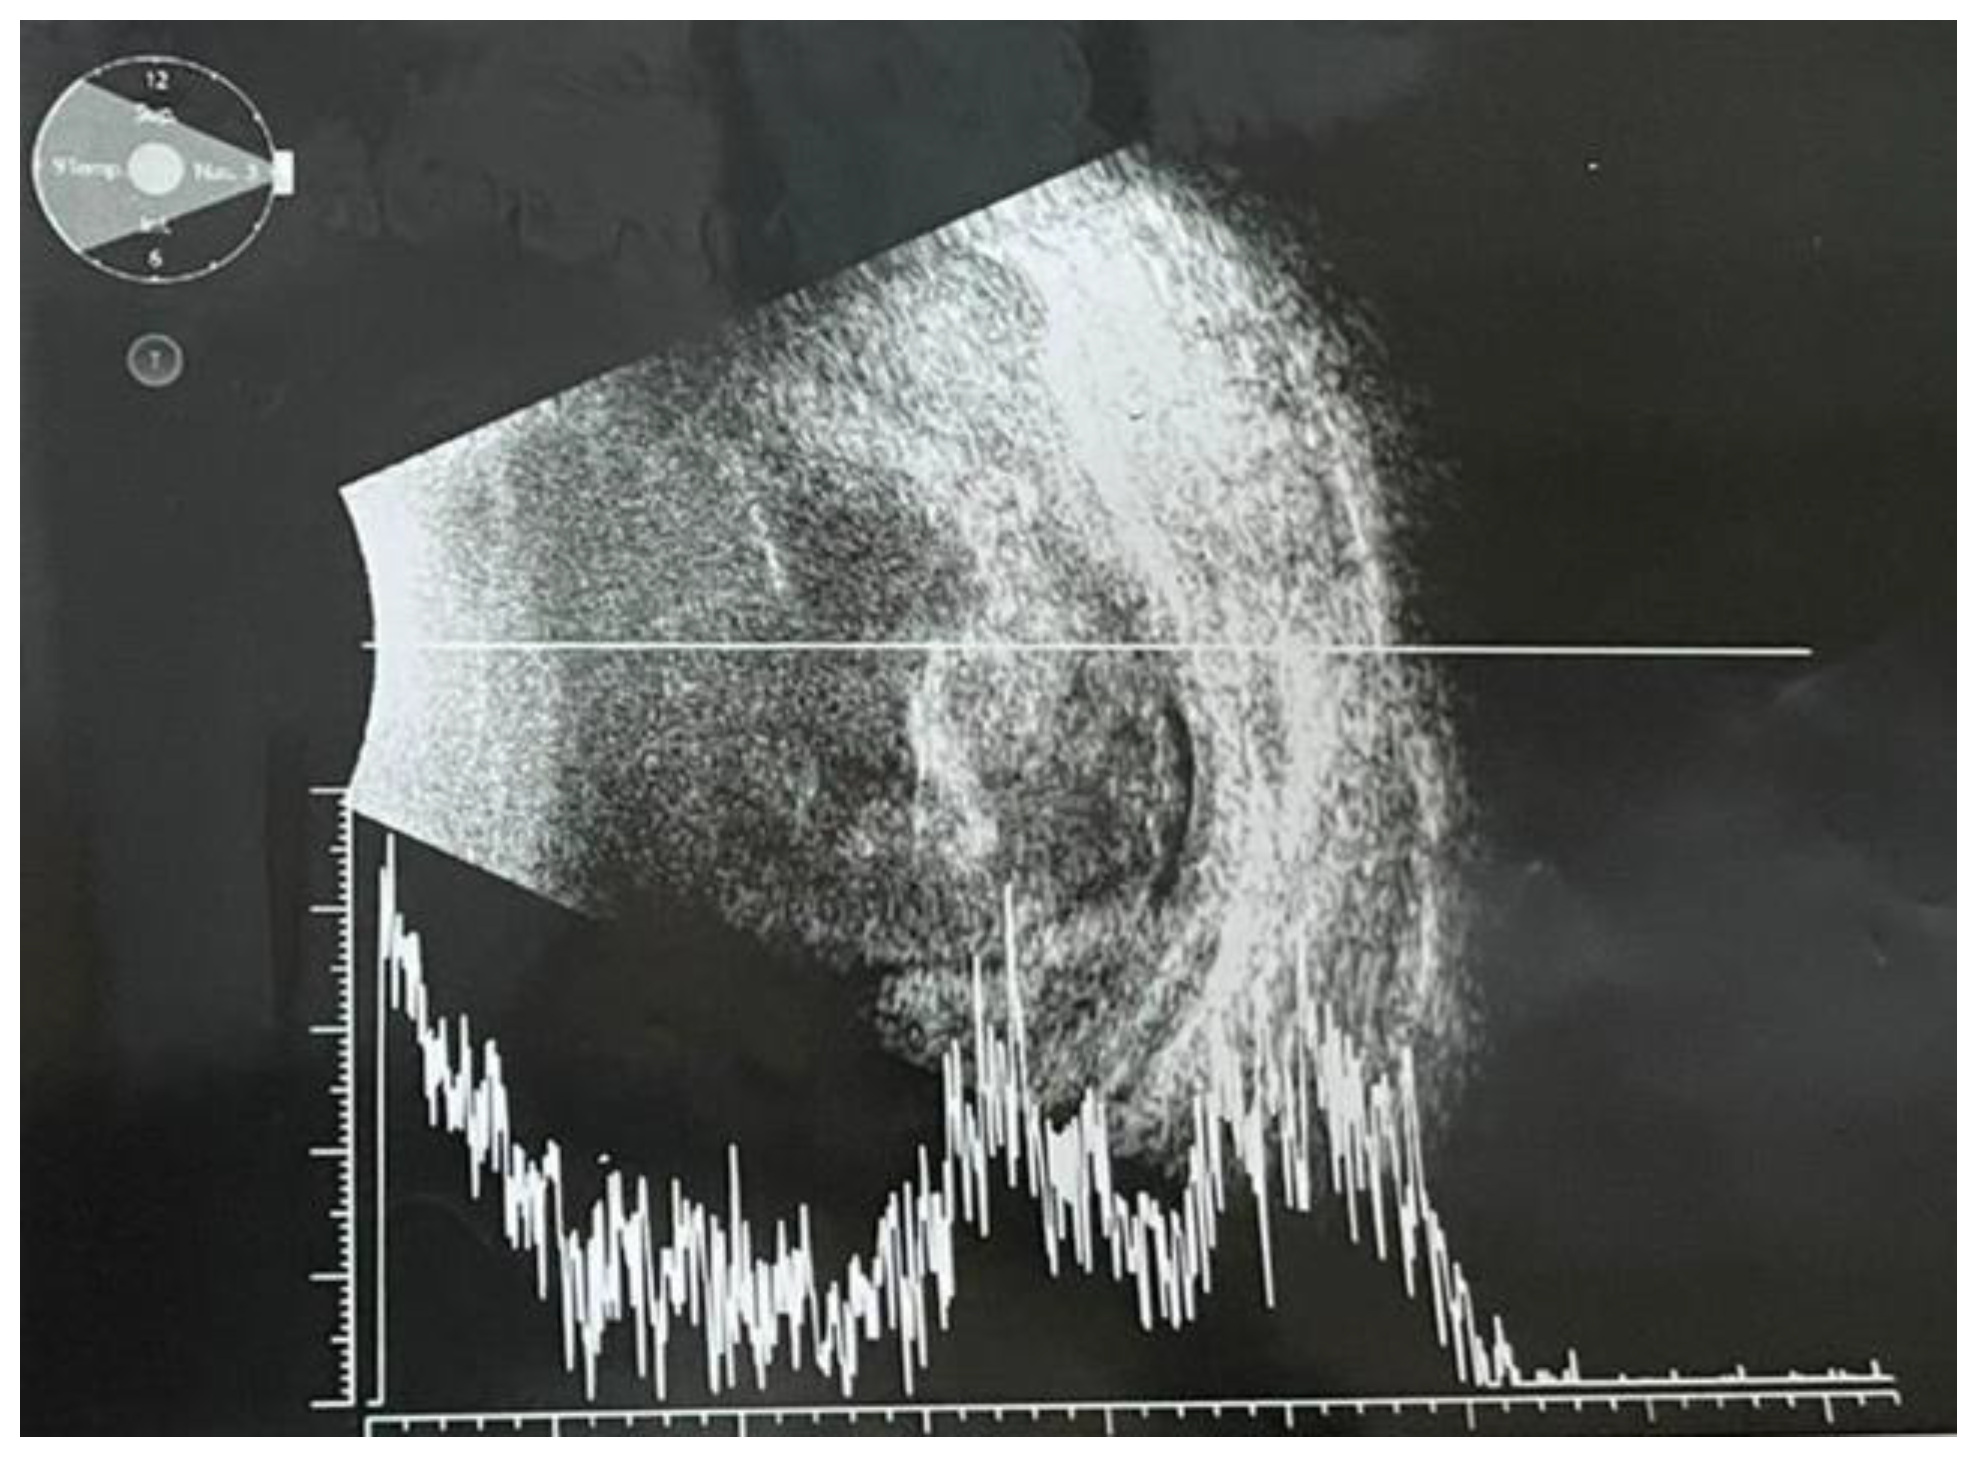

Ultrabiomicroscopy (UBM) confirmed posterior irido- lenticular synechiae on 360⁰ and thickening of the ciliary body (Figure 1). Ocular ultrasound exam revealed total retinal detachment, multiple fine vitreous echoes suggestive for vitritis, homogeneous thickening of the choroid and a 3mm diameter hyperechogenic mass invading sclera (Figure 2). A differential diagnosis between an extrascleral extension of an endophthalmitis and a possible intraocular tumor with scleral penetration was considered.

Figure 2.

Ocular ultrasonography (mode A/B): total retinal detachment, retinal and choroidal thickening; multiple densities in the vitreous body suggestive for vitritis; in the superior sector, a hypodense mass with loss of scleral echo and deformed ocular contour.